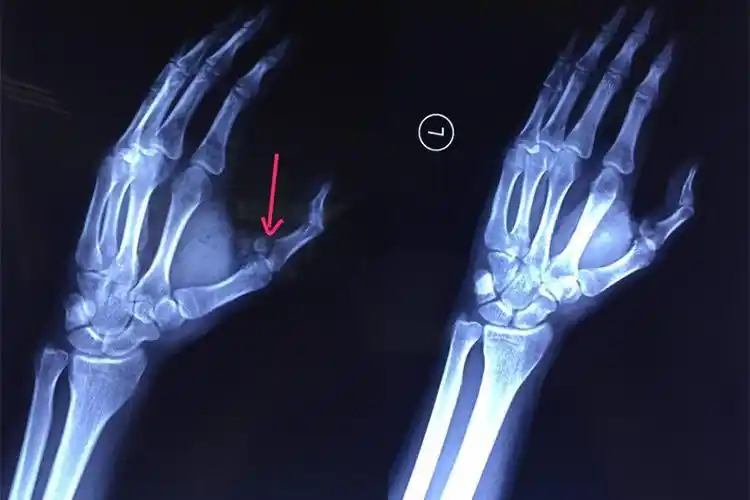

来医院急诊就诊,行x线片提示有右手中指第1节指骨近端骨折,涉及到关节

x光检查发现左手拇指骨折.(箭头所示)